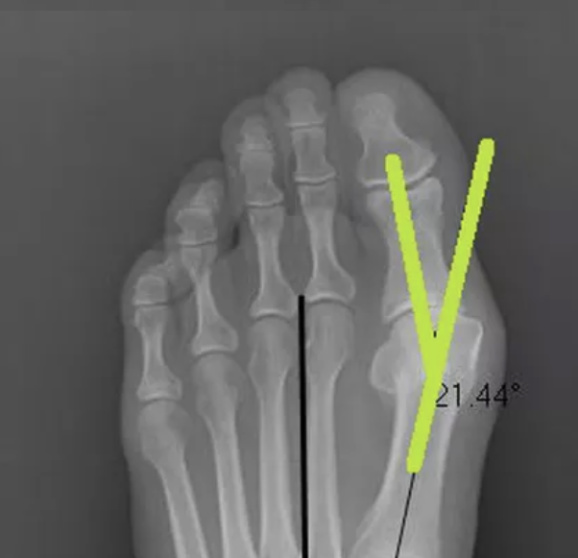

We completed a hands on joint assessment, which included an x-ray. This is Janine's initial x-ray. As you can see below, her x-ray shows that her bunion angle was 21 degrees. The ideal angle is 12-15 degrees.